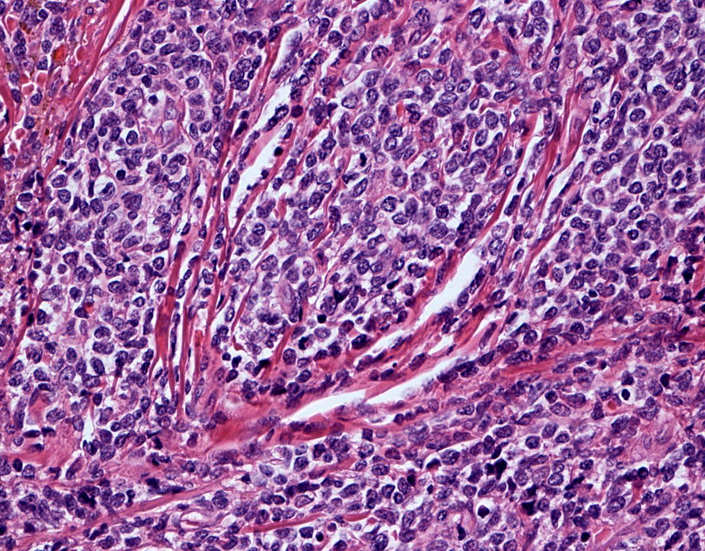

リンパ節病理組織所見

罹患リンパ節の基本構造は消失し腫瘍細胞のびまん性増殖で置換されている。非腫瘍性の小リンパ球(CD3+, CD4/8+)が濾胞様に散在して残る(Fig.01)。不整型または類円形の明るい核をもつmedium-sizeのリンパ球様細胞が密に増殖している。細胞質は乏しい(Fig.02)。CD68陽性macrophageが多く混在する部分が認められた。

Fig03, Fig04は腫瘍細胞の拡大像。大型異型細胞の出現が認められる。腫瘍細胞はCD4+, CD56+, CD123+